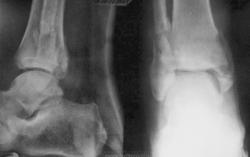

1. Консолидации конечно, такой как должно, нет. Вопрос1- почему не оперирован? Вопрос2-для себя, это последствия ДТП (ведь имееется "бампер-перелом")?

2. Сформированы "псевдоатрозы", наличиствует подвывих стопы наружу...пусть пьет дальше...авось "срастется"....

Обстоятельства травмы - упал с мотоцикла. Сразу не прооперировали потому-что: 1. Отказался от операции (См. пост Ольги Дмитриевны) 2. Стояние отломков после закрытой репозиции было вполне приличным (снимки у больного на руках, так что поверьте на слово). Ну а второй - пьяному, как известно, море по колено. Спасибо В.Л. за обработку снимков. Мне бы такую штуку.